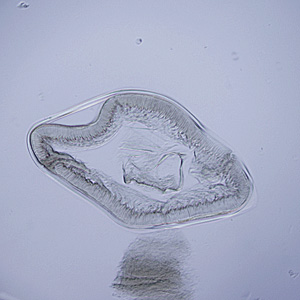

A small worm approximately 2.5 cm in length was recovered from the stomach of a 38-year-old male. The anterior end had been damaged by the extraction but it was sent to the CDC to see if it could still be identified. It was placed in lacto-phenol for clearing, after which it was still difficult to make a definitive identification. A small cross-section was made and examined using a compound microscope. The specimen in Figure A was captured at 40x magnification using brightfield illumination; the specimen in Figure B at 200x using differential interference contrast (DIC) microscopy. What is your diagnosis? Based on what criteria?

Figure A